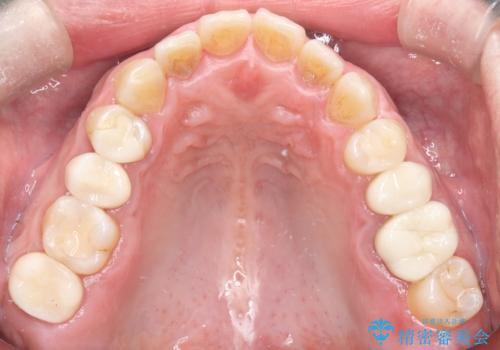

オールセラミックによる修復: 天然歯のような光の透過性と硬さを持つオールセラミックを使用しました。奥歯であっても、患者様固有の歯の色調や咬み合わせの溝を忠実に再現した修復物を装着。金属を一切使用しないことで、金属アレルギーのリスクを排除し、歯肉の色が黒ずむ心配もなくなりました。

【治療の結果】 全ての銀歯が白くなったことで、お口の中がパッと明るくなりました。見た目の美しさだけでなく、表面が滑らかなセラミックはプラークが付着しにくいため、将来的な虫歯や歯周病の予防効果も高まった健康的な口腔環境が実現しました。